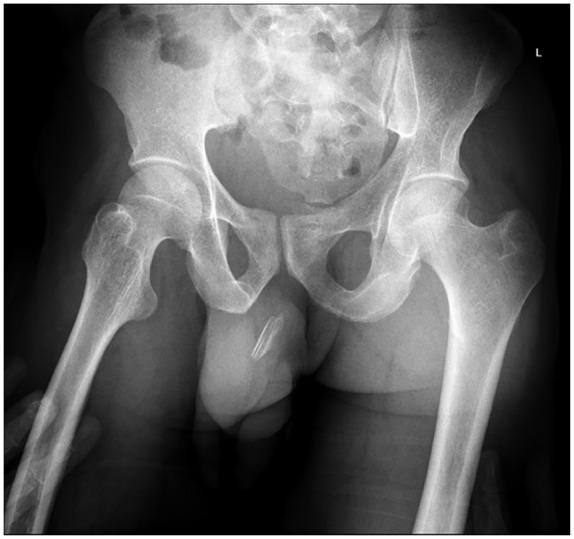

Urethral polyembolokoilamania, the self-insertion of a foreign body into the male urethra for sexual gratification and autoerotism, is an uncommon urological emergency with potentially severe consequences. We present the case of a 27-year-old male who presented to our emergency unit after apparently sustaining a penile injury during sexual intercourse. Clinically, a foreign body was thought to be palpable, extending from the mid-shaft of the penis to the penoscrotal junction. Pelvic X-rays confirmed a radiopaque penile foreign body in the region of the anterior urethra. Cystoscopy confirmed the presence of an encrusted foreign body in the anterior urethra. It noted that the surrounding mucosa was very inflamed with areas of necrosis, suggesting that the foreign body had been present in the urethra for some time. To avoid further urethral trauma, we approached the foreign body an external urethrotomy and removed a plastic knife in three parts. The urethra was repaired over a 16F catheter. The patient had an uneventful postoperative course, and a peri-catheter urethrogram 6 weeks after the procedure showed no signs of contrast extravasation or urethral stricture.

尿道多栓塞癖,即男性为获得性满足和自体性欲而将异物自行插入尿道,是一种罕见的泌尿外科急症,可能会导致严重后果。我们报告一例27岁男性病例,该患者在性交过程中阴茎明显受伤后前来我院急诊科就诊。临床上,可触及一个异物,从阴茎中段延伸至阴茎阴囊交界处。盆腔X线检查证实前尿道区域有一个不透X线的阴茎异物。膀胱镜检查证实前尿道存在一个有结痂的异物。检查发现周围黏膜严重发炎并有坏死区域,提示异物已在尿道内存在一段时间。为避免进一步的尿道创伤,我们通过尿道外切开术处理异物,并分三部分取出一把塑料刀。在16F导管支撑下修复尿道。患者术后恢复顺利,术后6周的导管周围尿道造影显示无造影剂外渗或尿道狭窄迹象。